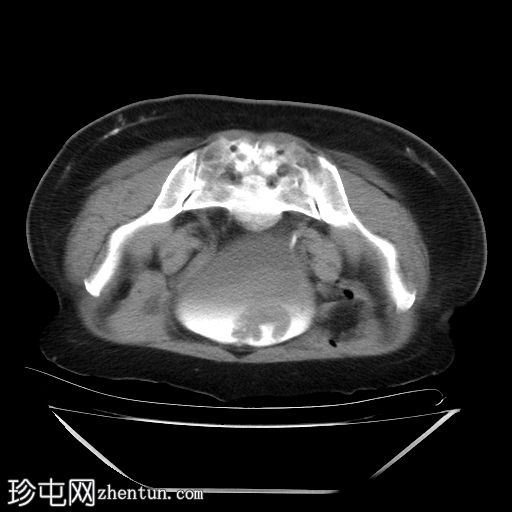

膀胱造影(静脉注射造影剂)

CT

轴位

平扫

膀胱内可见一边界清晰、不规则、可移动的软组织病变(CT值65 HU),直径约40 mm。病变无钙化,增强扫描后无强化。首要鉴别诊断为血肿。

采用俯卧位CT扫描显示病变活动度。

膀胱镜检查证实存在血肿,并进行了血块清除术。

膀胱血肿常被误诊肿瘤性肿块。俯卧位是区分可移动血块和固定于膀胱壁的肿瘤的关键操作。这种简便的技术,结合无对比剂增强,可提供强有力的非侵入性证据,排除肿瘤性病变。